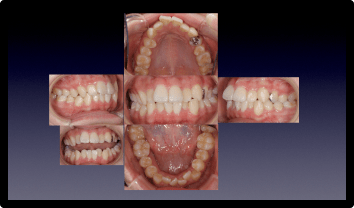

開咬を矯正治療で改善した症例

BEFORE

AFTER

症例概要

年代・性別

20代 女性

主訴

前歯噛んでない、麺類噛みにくい、息が漏れる

治療内容

インビザラインライト

治療期間

7ヶ月

治療のリスク

歯が染みたり、後戻りする可能性があります /div>

治療費用

495,000円(税込)